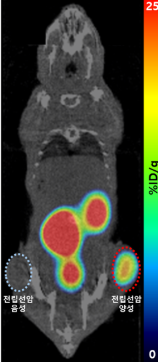

사진4. 전립선암 음성 대조군과 양성 실험군이 심어진 쥐에 주입한 갈륨-68 PSMA-11 체내영상

※ PSMA, prostate specific membrane antigen (전립선특이막항원)

설명 : 전립선암 음성 대조군과 달리, 우측 허벅지의 양성 실험군의 종양 부위에만 갈륨-68 방사성의약품이 선택적으로 집적되며 갈륨-68 발생기의 유효성을 성공적으로 검증

□ 또한 연구진은 이번에 개발된 소재로 용출한 갈륨-68을 이용해 분당서울대병원 핵의학과와 공동으로 전립선암 진단용 방사성의약품의 비임상 실험을 수행하여, 종양 영상 확보를 통해 갈륨-68 발생기 핵심 소재의 유효성을 성공적으로 검증했다. 해당 기술은 국내·외 특허등록을 완료했으며, 향후 방사성의약품을 개발하는 국내 기업에 기술이전이 추진될 예정이다.